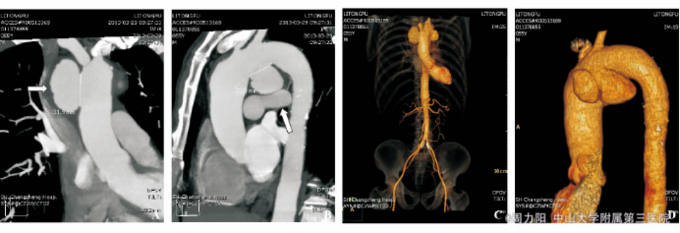

查体:体温36.5℃,心率80次/min,律齐,血压130/80mmHg,双上肢血压相同。心前区无隆起,心尖搏动增强,心浊音界向左下方略扩大,主动脉瓣区可闻及收缩期3/6级隆隆样杂音。无心包摩擦音,未及水冲脉等周围血管征。 辅助检查:血甲苯胺红不加热血清试验(TRUST)1∶128+,血梅毒螺旋体颗粒凝集试验(TPPA)+。脑脊液TRUST、性病研究实验室试验(VDRL)阴性。血压、血脂、免疫指标、肿瘤标志物、红细胞沉降率、C-反应蛋白未见异常,G试验、结核抗体(-)。患者的妻子及其他家庭成员:梅毒血清学及HIV均阴性。心超:升主动脉远端及主动脉弓起始部瘤样扩张,主动脉壁粗糙,轻度肺动脉高压伴三尖瓣返流。全主动脉CTA:升主动脉及主动脉弓见多发瘤样膨出,扩张管径分别为49.1、33.9和19.2mm,全主动脉管壁内见软硬斑块,部分见钙化影。

根据患者进行性声音嘶哑,心脏杂音,主动脉造影的动脉瘤的部位、形态均符合梅毒性主动脉瘤的特点,梅毒血清学试验阳性,故诊 断为“梅毒性主动脉瘤”. 治疗:患者青霉素皮试阳性,故予头孢曲松第1天0.2g,第2天0.4g,第3天0.8g,第4天起2g/d,共2周,治疗前1天开始予泼尼松10mg2/d,口服,共3d,并控制血压、血脂,抗血小板聚集。后于血管外科行血管支架植入术。